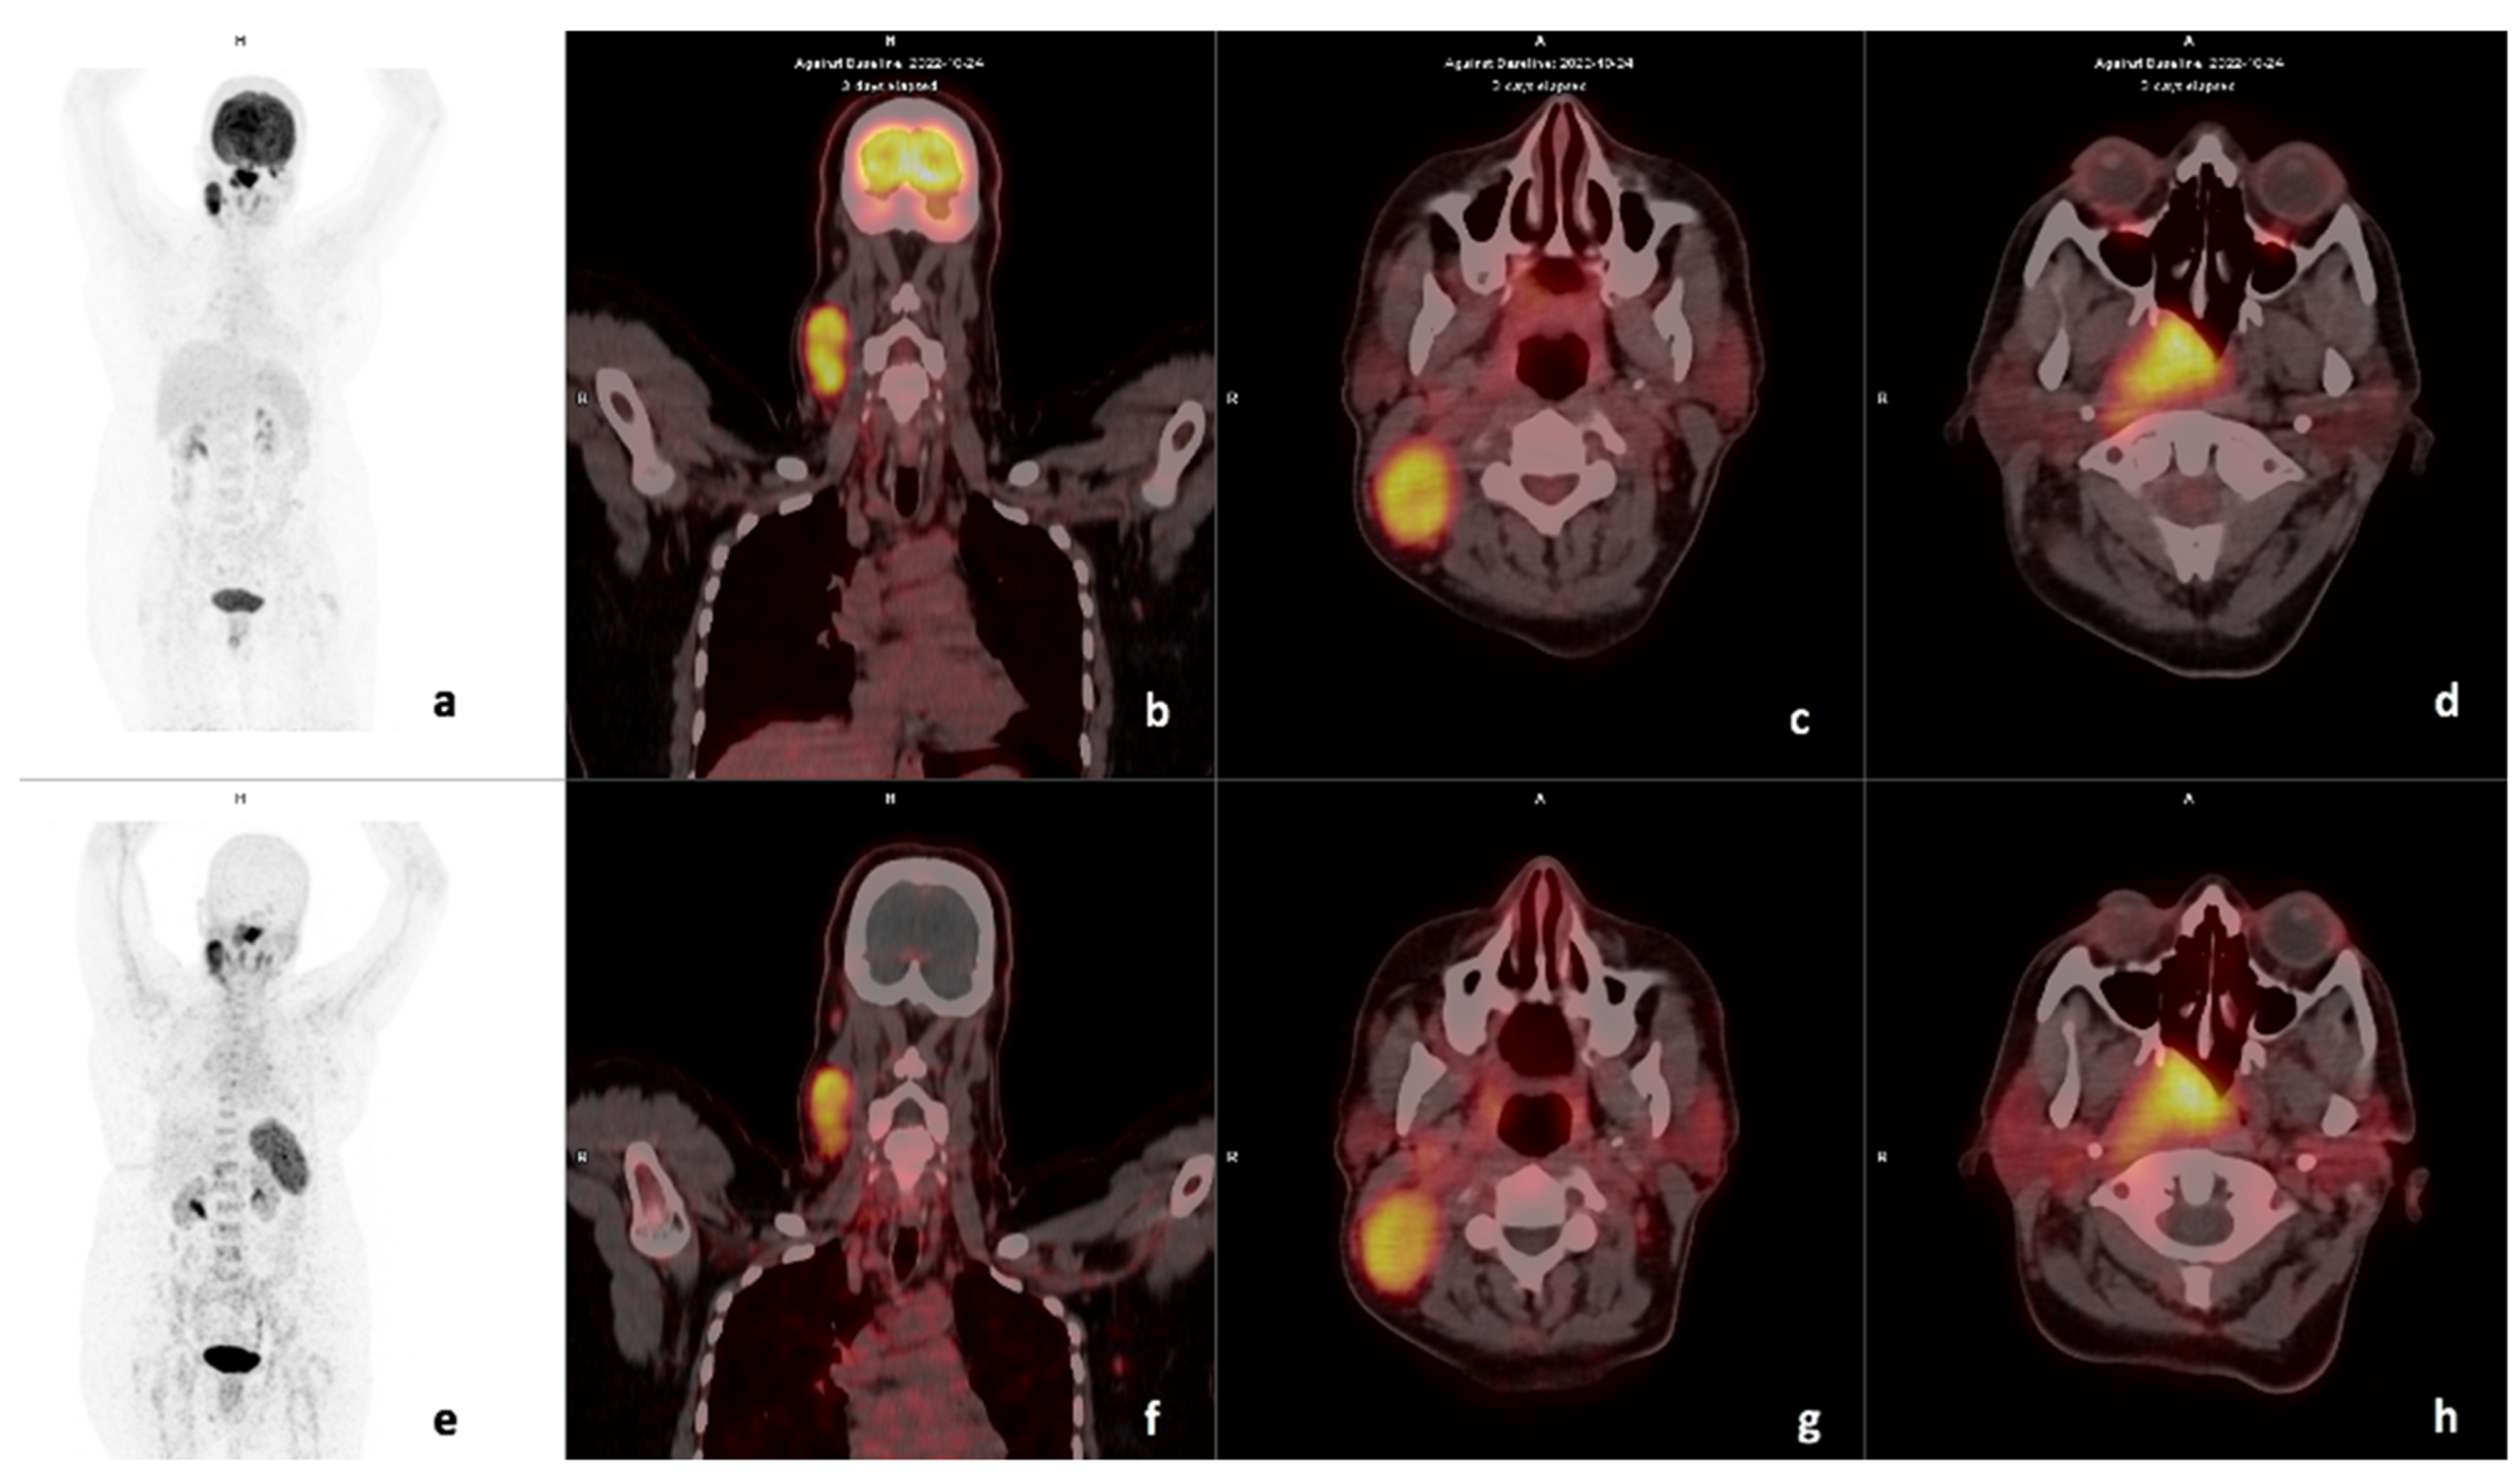

3.2. Comparison of FDG and 68Ga-Pentixafor

3.3. Visual Analysis